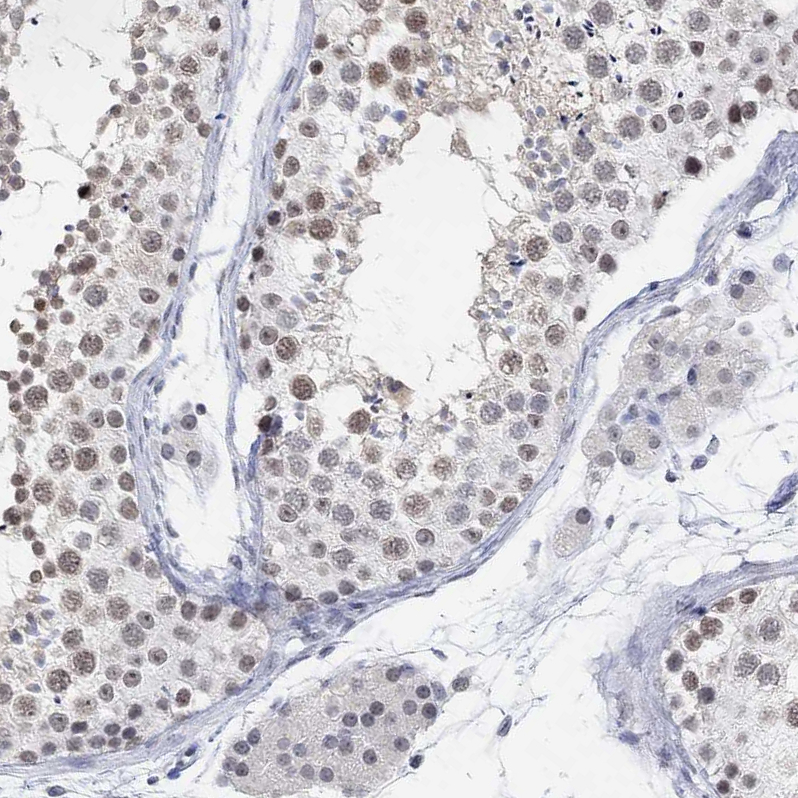

Immunohistochemistry analysis in human cerebral cortex and liver tissues using HPA047746 antibody. Corresponding PURG RNA-seq data are presented for the same tissues.